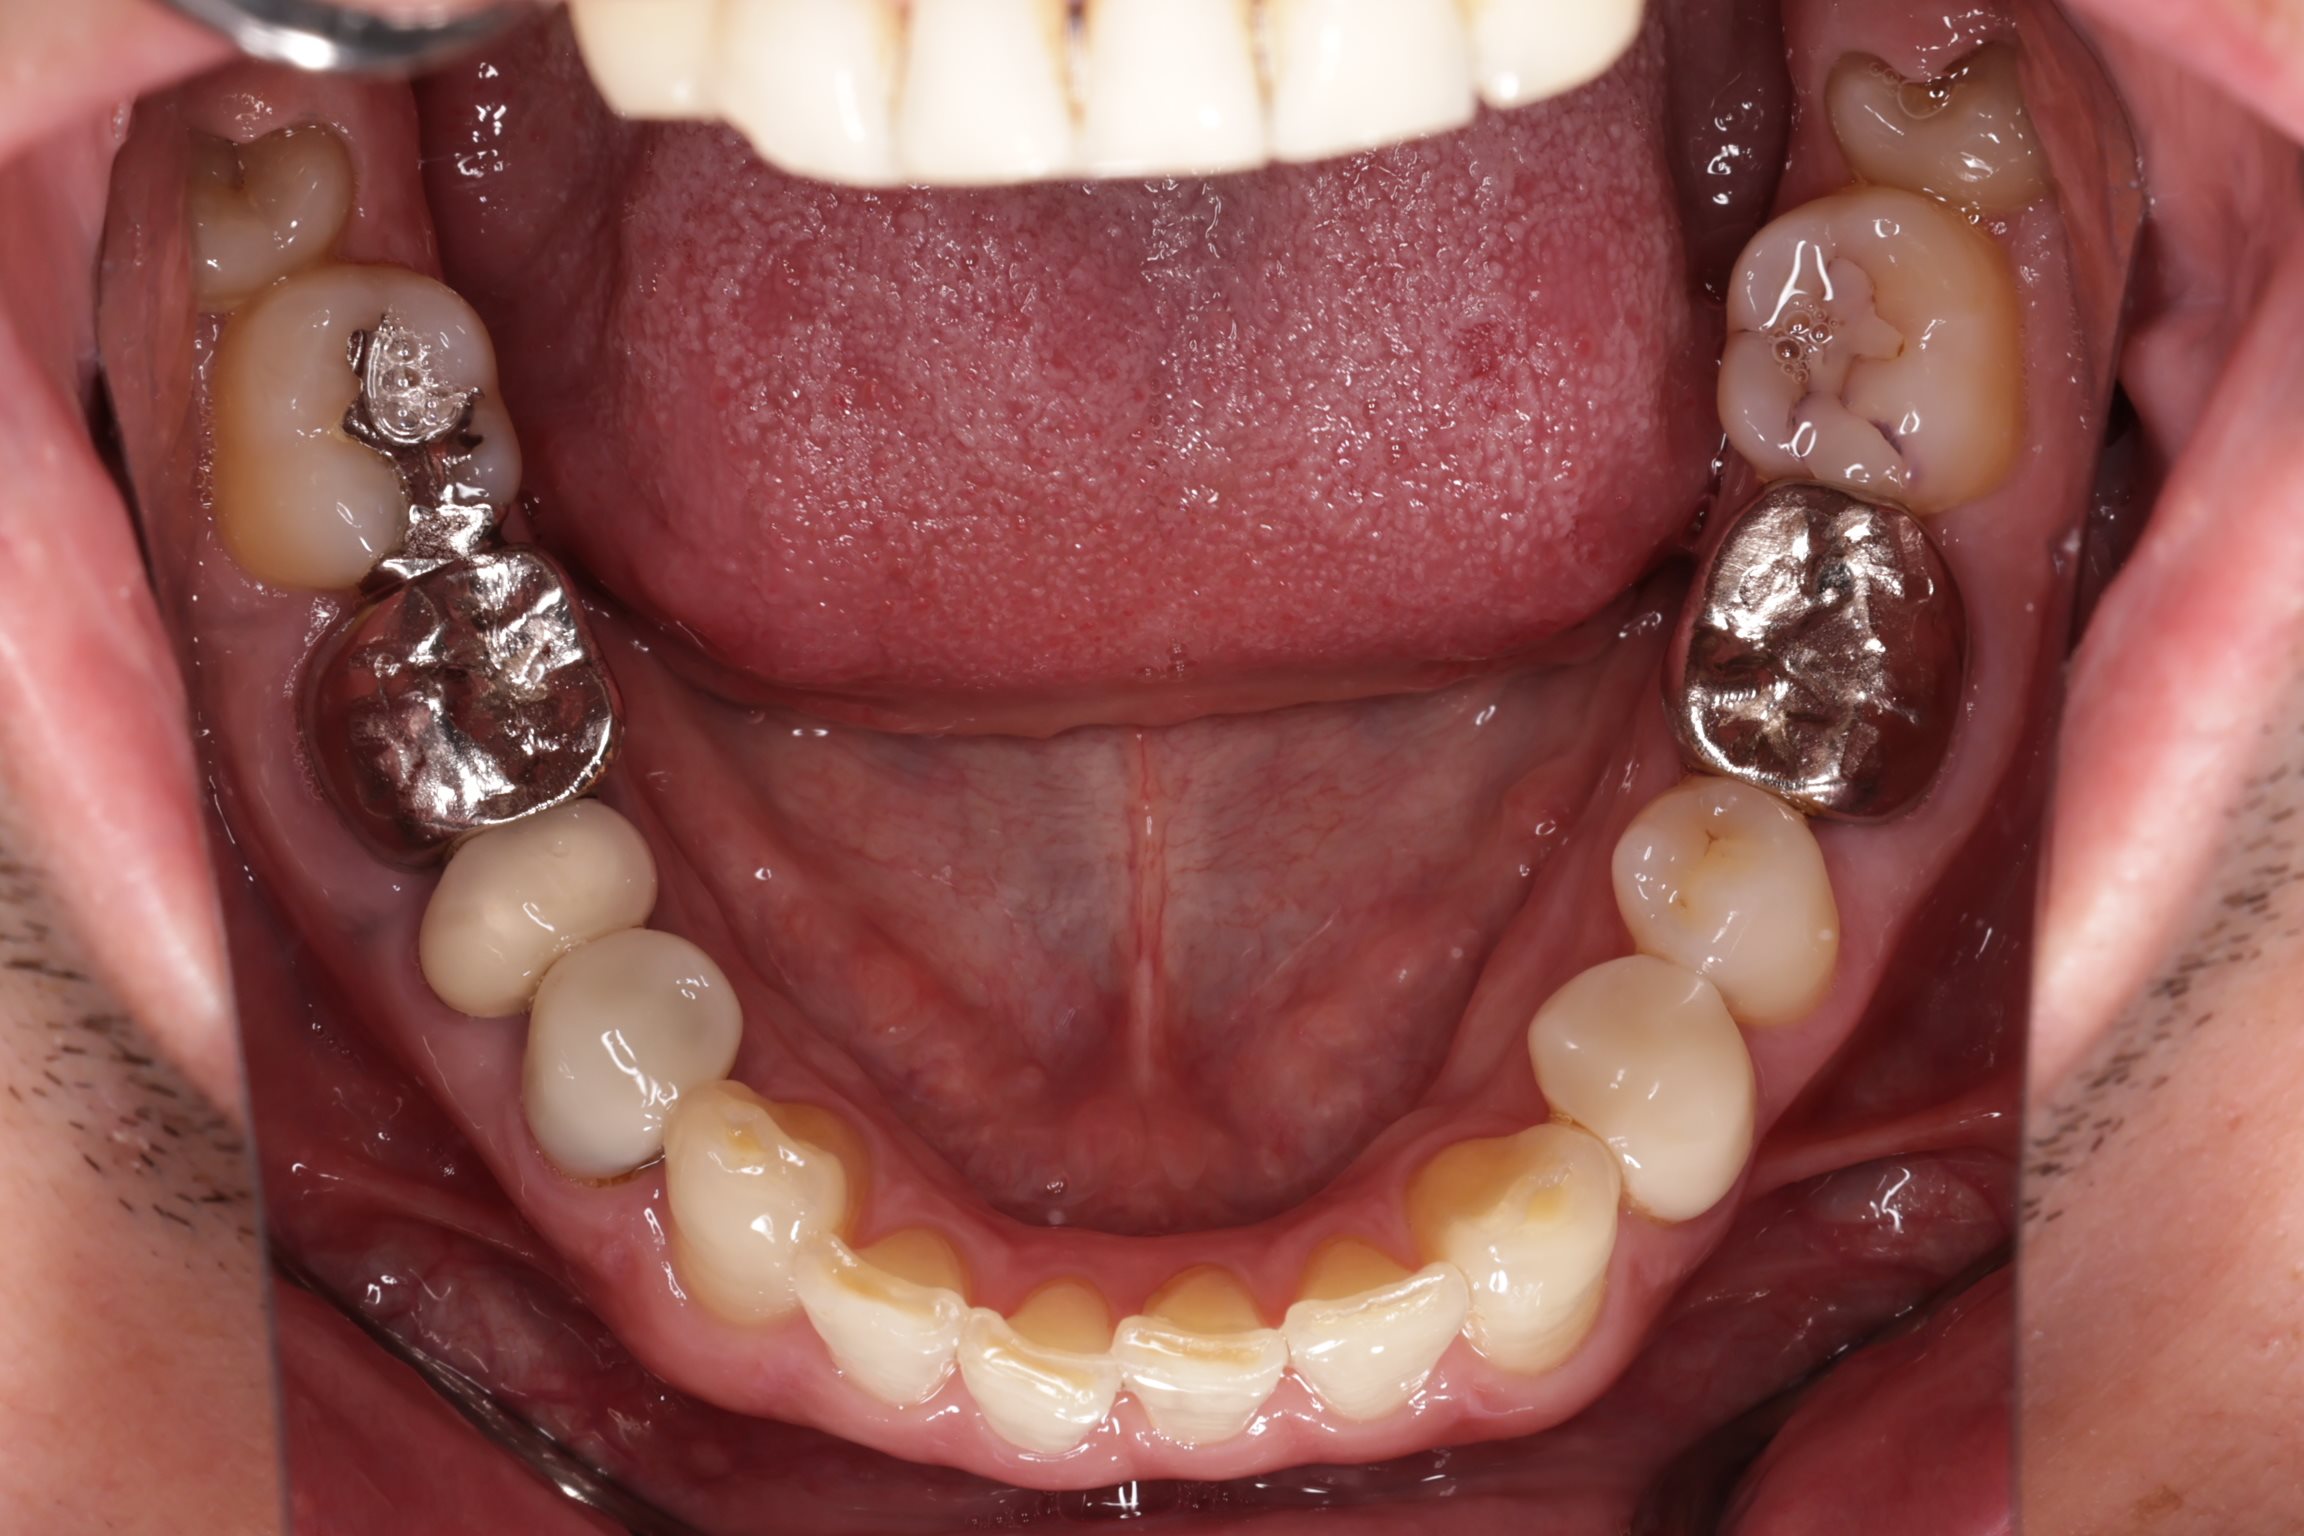

初診時の口腔内の状態:

口腔内には多数の銀歯(銀合金)が確認されました。患者様は過去に多くの虫歯治療を受けており、そのほとんどが保険適用内の銀合金で修復されていました。

患者様はパッチテストによりニッケルなどに対するアレルギーを持っていることが確認されており、口腔内の銀合金もアレルギーの原因となっている可能性が高いと診断しました。また、レントゲン画像を確認すると、被せ物や詰め物の内部、あるいは隙間から、虫歯(カリエス)や根の細菌感染が疑われる状態も確認されました。

一部の歯(右下の5番目)については、銀歯の詰め物の隙間から細菌が侵入し、歯の根の中が細菌感染している兆候が見られたため、この機会に歯の内部の消毒(根管治療)を挟んで処置を行いました。